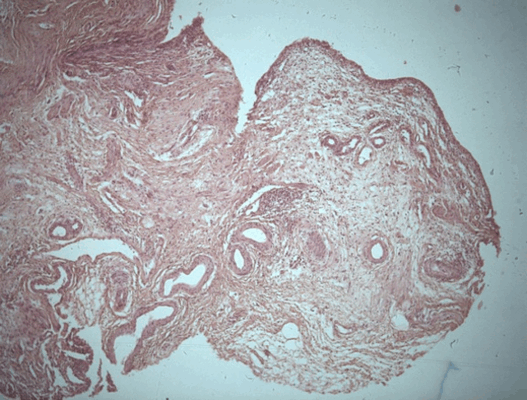

Патоморфологическое исследование пациента С.

Морфологическая картина полипоидного цистита. Окраска гематоксилин-эозином, х5

Патоморфологическое исследование пациентки К.

Полипоидный цистит является реакцией на травму слизистой оболочки, цистоскопически и гистологически симулирует различные уротелиальные неоплазии. Цистоскопическая картина полипоидного цистита характеризуется образованием полипоидных и папиллярных выростов, располагающихся на широком или узком основании, буллезных полипов, трабекулярности, диффузной гиперемии, отека слизистой мочевого пузыря. Патоморфологическая картина полипоидного цистита характеризуется наличием нормального или гиперплазированного уротелия, наличием признаков острого и хронического воспаления, реактивной уротелиальной атипией, отеком собственной пластинки слизистой с фиброзом и полнокровными сосудами. За счет выраженного отека собственной пластинки формируются характерные полипоидные выпячивания. При патоморфологическом исследовании у всех пациентов обнаруживают эозинофильные инфильтраты, как вторичную реакцию на токсические или аллергические эффекты уретрального катетера.